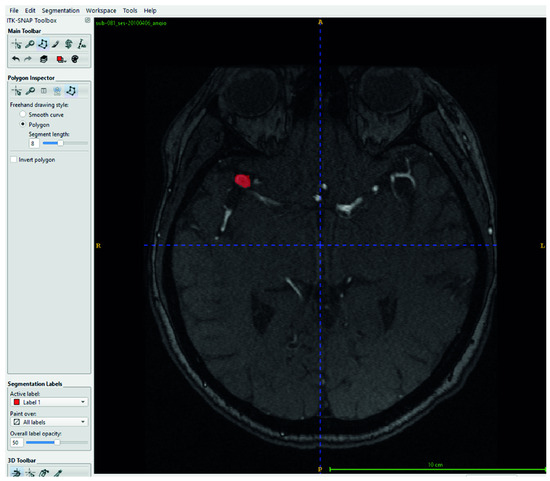

Magnetic resonance imaging (MRI) is a medical imaging technique used in radiology to generate pictures of the anatomy and the physiological processes inside the body. MRI scanners use strong magnetic fields, magnetic field gradients, and radio waves to form images of the organs in the body. The technology continually evolves as groundbreaking innovations and applications emerge. For example, some researchers use non-contrast MRI surveillance of craniopharyngiomas; some researchers found that by employing the spherical mean MRI technique, they can detect the IDH status in brain gliomas; and some researchers utilize generative artificial intelligence to transform grayscale MRI images into colour. This helps us to better understand multiple sclerosis, among other diseases.